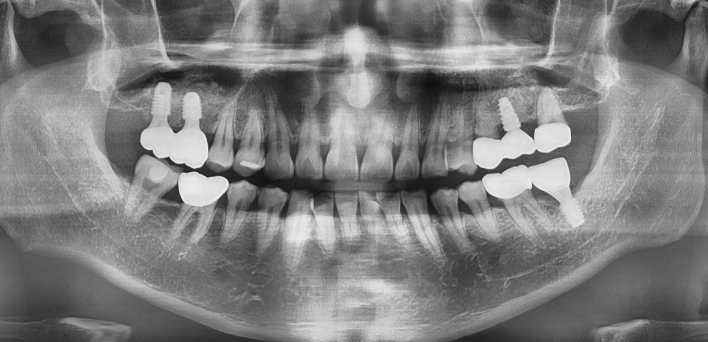

임플란트 : 손 ** 님 (50대)

치아가 있다는게, 아직도 정말 꿈만 같아요.

Before Before

2020.02.30

After After

환자 특징01무치악 상태

환자 특징02수년간 무치악으로 지내심

임플란트가 불가능할것이라

생각하고 내원

위, 아래 6개씩 식립

디지털 풀아치 임플란트